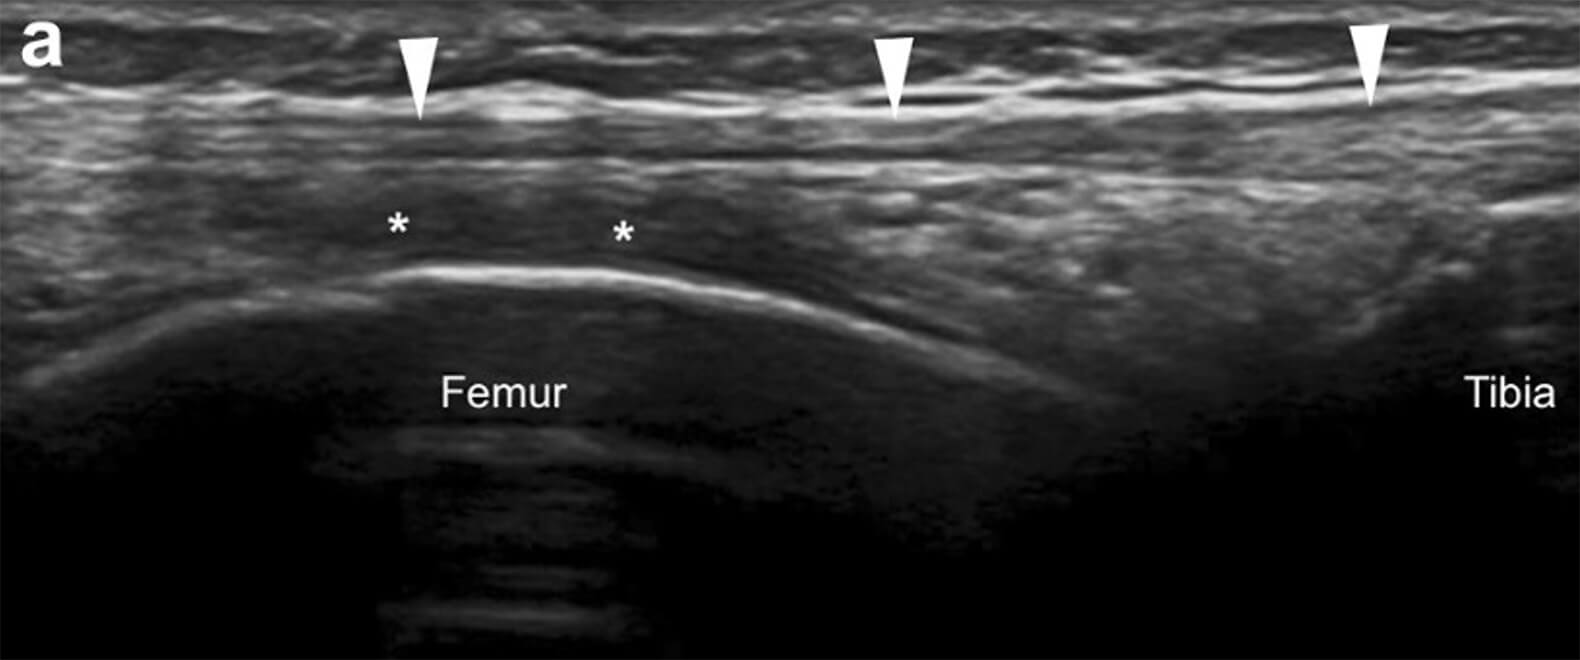

Echografie

Met een echo is de dikte van de peesplaat aan de zijkant van de heup ter hoogte van de klachten te meten. Op deze locatie kan de peesplaat verdikt zijn. Ook is het mogelijk om vocht te zien net onder de peesplaat, wat met of zonder slijmbeurszwelling kan voorkomen. Een echo is ook nuttig als er twijfel is over de diagnose, want hiermee zijn ook andere oorzaken van de klachten in beeld te brengen.

Een blik met de echo op de zijkant van het bovenbeen rond de knie, waarbij de peesplaat met witte driehoekjes wordt aangegeven en het vocht onder de peesplaat met een * (Jimenez Diaz et al. J Ultrasound 2020).